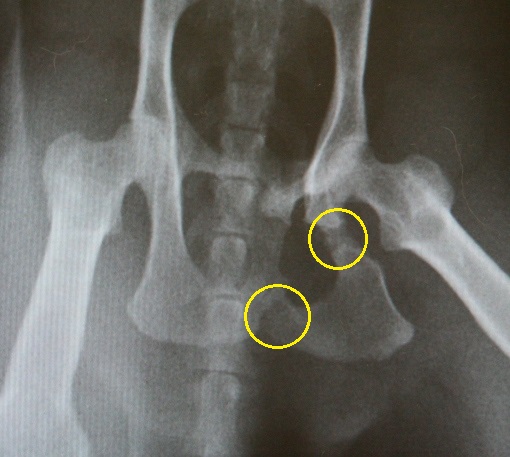

骨盤骨折していた事が判明

判り易く、骨折箇所に印を付けると、この部分

しらたまちゃんは、病院では、出されたご飯をもの凄い勢いで食べつくし、何度もお代りの催促をして、出されたご飯を又、食べつくす、という行動をしたそうで、どうも、何かおかしい、と先生が気づかれ、レントゲンを撮ったところ骨盤骨折した痕跡があり、骨折自体は、自然治癒した状態だそうですが、これが原因で、巨大結腸症になってしまったのだろう、との事。

骨盤骨折が原因での巨大結腸症の為、便秘気味になったり、下痢気味になったり、排便困難になったりする為、食事のケア、排便のケアを小まめに出来る家庭環境で無いと、しらたまちゃんを家族に迎え入れる事は、非常に難しい、との先生の判断がなされ、結果、我が家の子にする事は不可能になっていました。